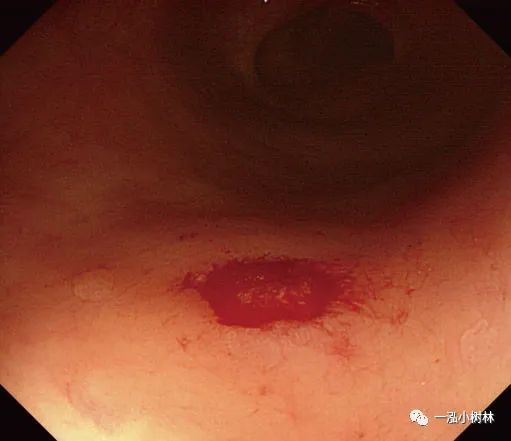

图4b 直肠5mm大小Is型无蒂腺瘤

图4c 同一病变的NBI图像

图4e 圈套病灶包括周围1-2mm正常黏膜

图4f 切除标本保留在息肉切除部位

图4 g息肉摘除术后创面